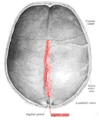

![]() Human adult skull from above. Sagittal suture labeled at center. | |

The sagittal suture is a dense, fibrous connective tissue joint between the two parietal bones of the skull. The term is derived from the Latin word sagitta, meaning arrow. The derivation of this term may be demonstrated by observing how the sagittal suture is notched posteriorly, like an arrow, by the lambdoid suture. The sagittal suture is also known as the interparietal suture and the sutura interparietalis.

Two anatomical landmarks are found on the sagittal suture: the bregma, and the vertex of the skull. The bregma is formed by the intersection of the sagittal and coronal sutures. The vertex is the highest point on the skull and is often near the midpoint of the sagittal suture.